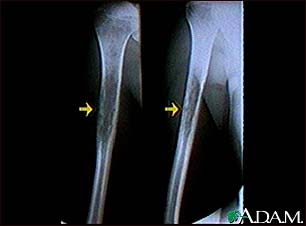

Ewings sarcoma - X-ray

This x-ray shows a malignant bone tumor (Ewing's sarcoma) of the upper arm bone (humerus). This type of tumor usually occurs during childhood and adolescence.